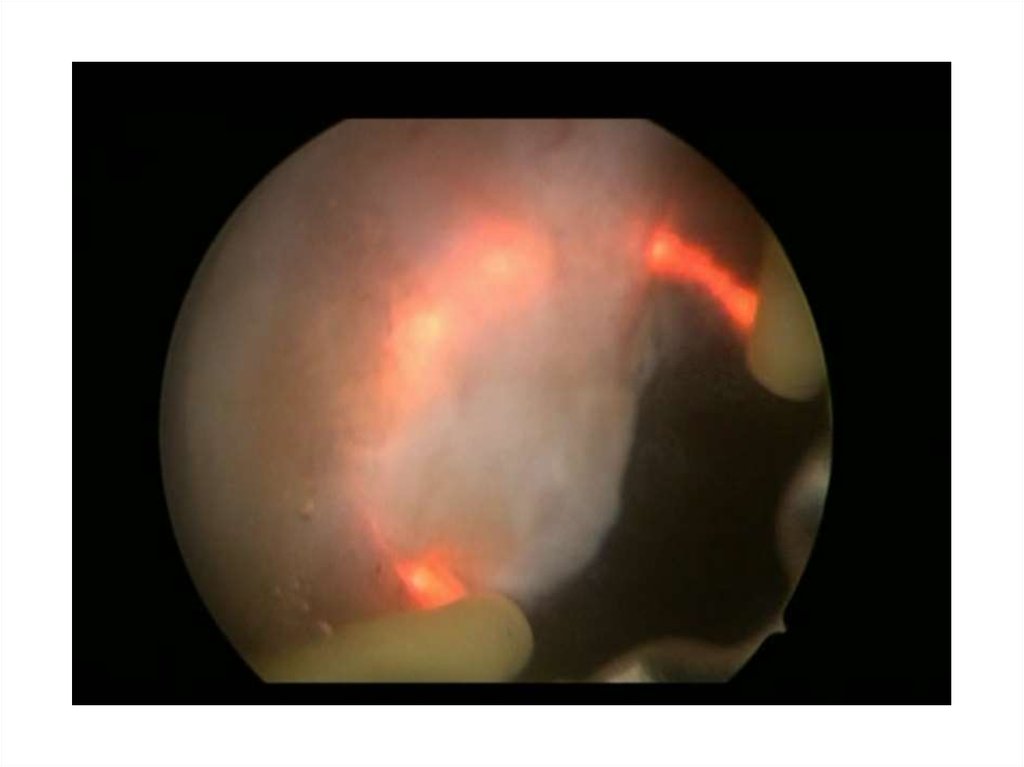

8. Кузнецов В.А. 59лет

• 13.11.14 – лазерная энуклеация ГПЖ

• 26.10.15 – ТУР шейки мочевого пузыря

• С января 2016 года отмечает ухудшение

качества мочеиспускания